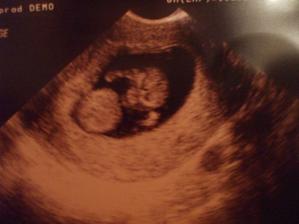

no vcera som zistila ze uz som v 11-tom tyzdni...takze na fotke som bola v 9tom 🙂